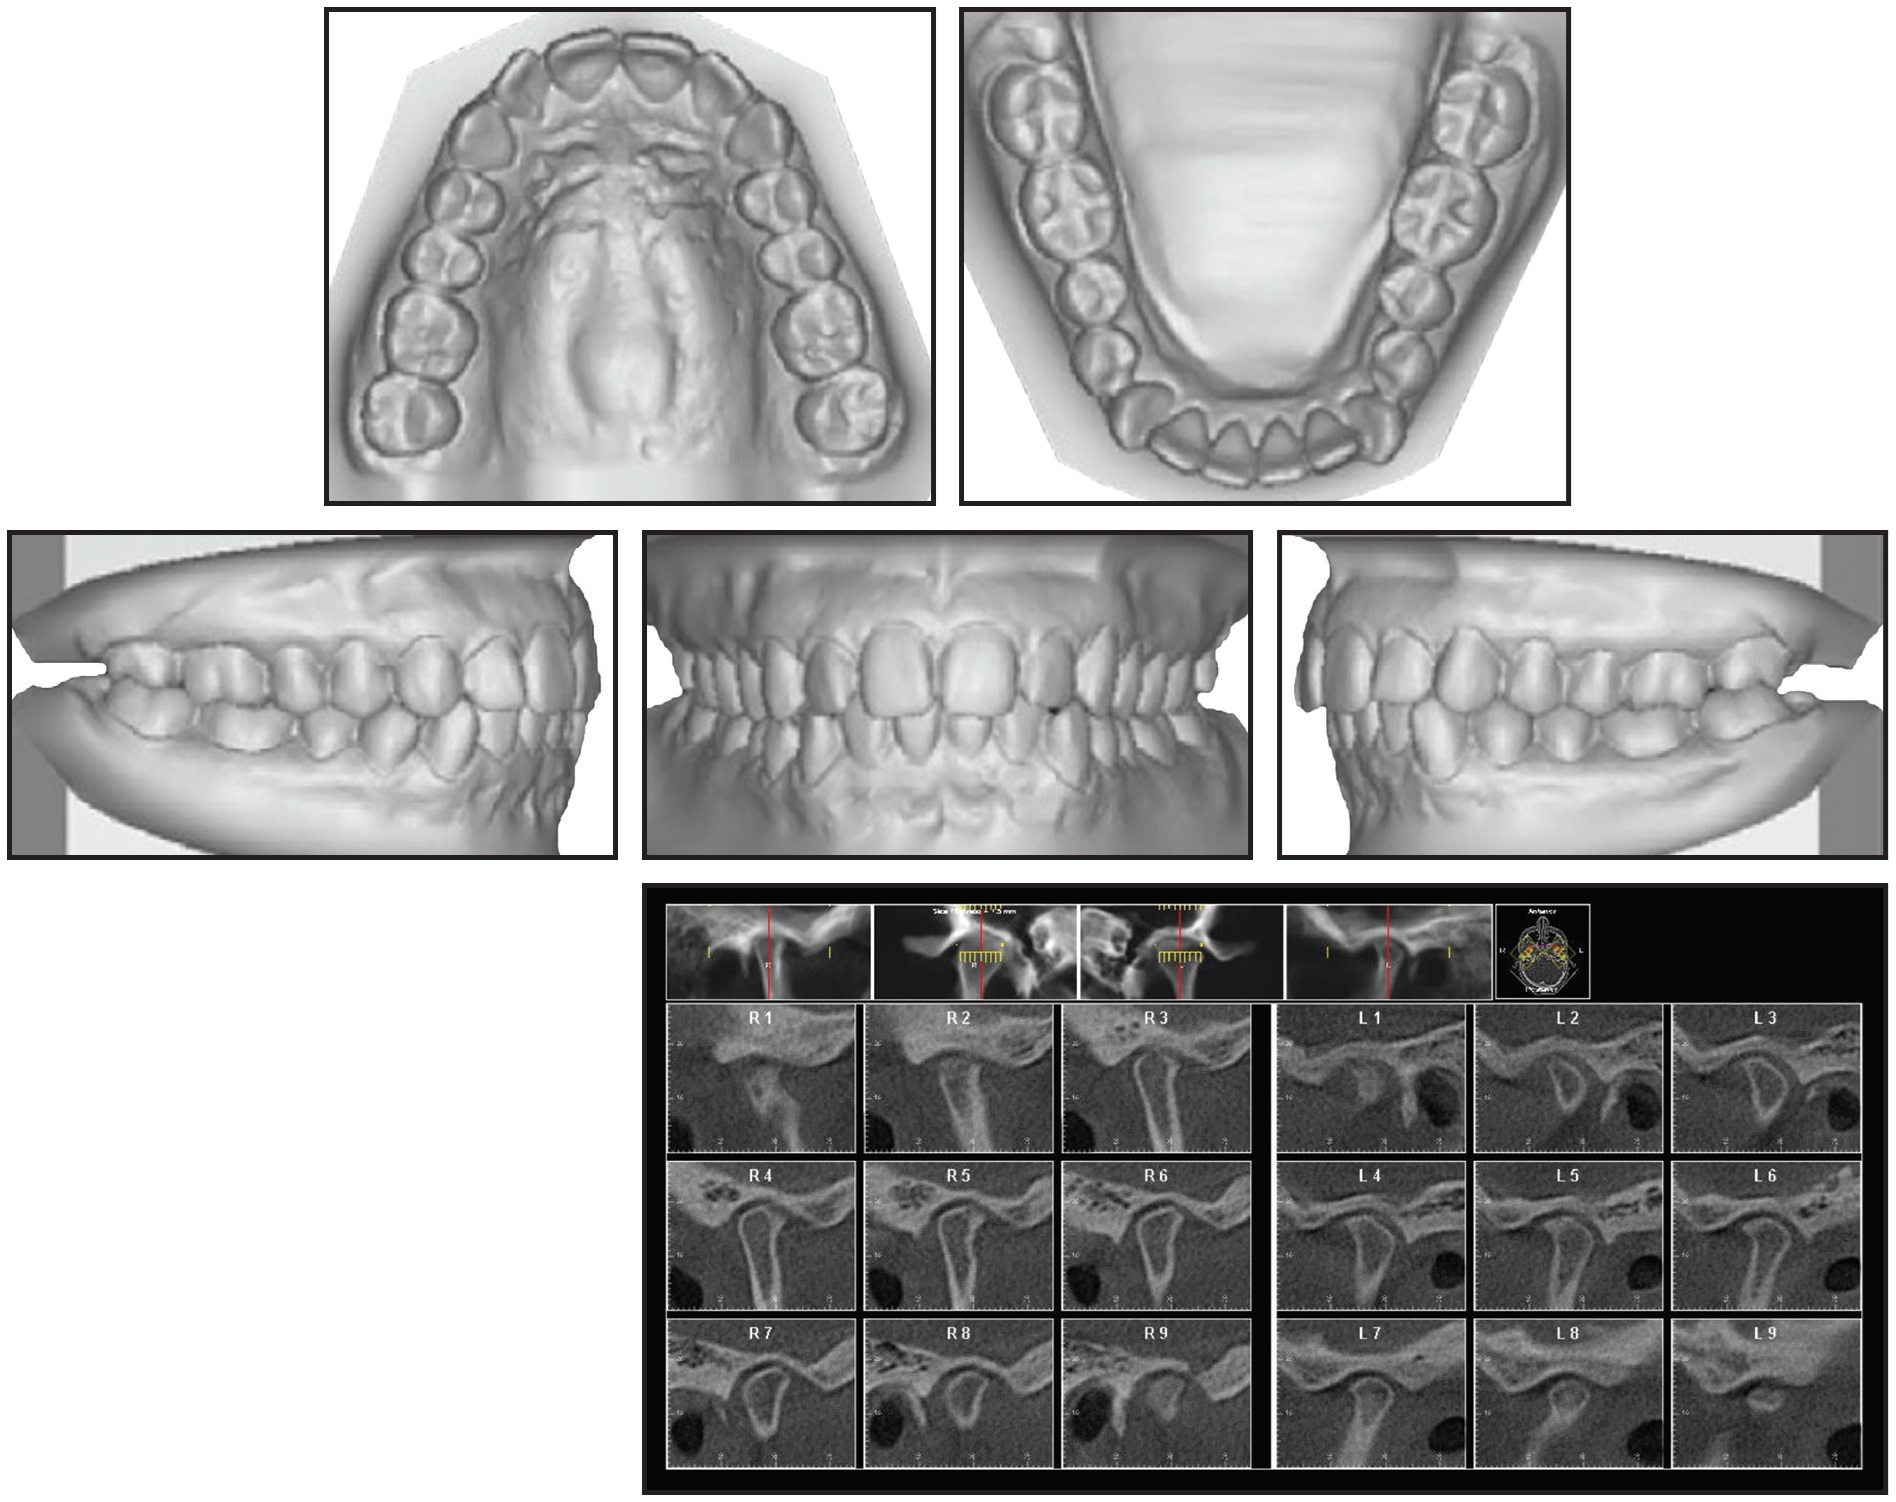

In our patient, we suspected bilateral disc displacement with reduction because most patients with TMD symptoms demonstrate reducing discs.16 Magnetic resonance imaging (MRI) can be used before treatment to establish a differential diagnosis. An MRI may also be taken after use of an anterior repositioning appliance to confirm disc recapture. Patients with reducing discs show a 91% recapture rate when the condyle is moved into the proper Gelb 4/7 position (Fig. 11) with an anterior repositioning appliance, as evaluated by MRI.4

Our patient was placed in a musculoskeletally stable position with a bilateral manual manipulation technique, which is described by Okeson as a method of moving the condyles into their most superoanterior positions when the mouth closes.17 Clinically, this manipulation eliminated the TMJ clicking and popping in our case. A bite registration was then made in centric relation (Fig. 2), since the coincidence of centric occlusion with centric relation is of paramount importance as the teeth guide the condylar axes.18

Fig. 11 Gelb diagram of proper 4/7 condyle/fossa relationship.